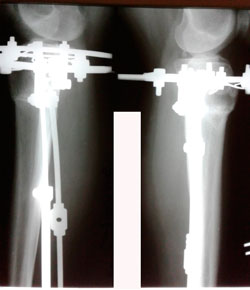

Исходник - 35 лет.

Дата операции - 21.01.2020

IMG_8372-20-01-20-04-59.JPG

IMG_8374-20-01-20-04-59.JPG